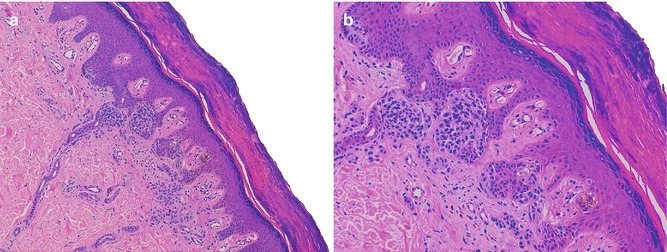

Fig. 7.3

(a, b) Cryobiopsy. Compound melanocytic nevi. Absence of the artifactual changes. Hematoxylin-eosin stained. Original magnification: 1: 100×; 2: 200×